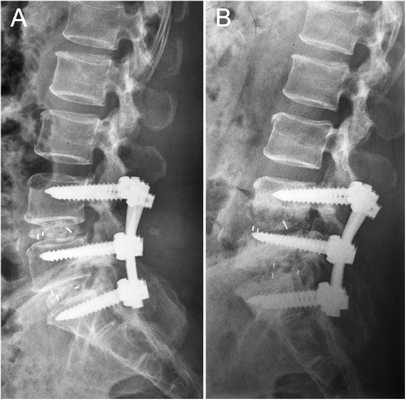

Стабилизация поясничного отдела.

Коррекция кифоза грудного отдела.